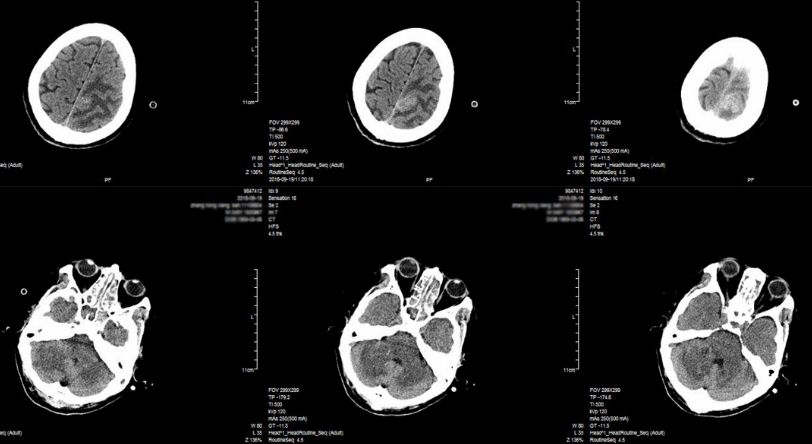

患者3月前发热后出现行走不稳,走路摇晃,伴口齿不利,偶有饮水呛咳,间歇发热,具体体温不详。 2月前症状逐渐加重,至外院就诊,头颅增强MRI:延髓、桥脑、中脑和桥小脑臂异常信号。诊断为“颅内多发病灶(脑干、小脑),代谢、炎症首先考虑,肿瘤不排除”(图1),入院后脑脊液检查:蛋白72.7mg/dL,有核细胞10/ul,墨汁染色及抗酸杆菌染色阴性。予呋喃硫铵、弥可保营养神经治疗,症状稍好转后出院,但仍间断发热。近1月来病情复发加重,来浙医二院就诊,头部增强磁共振显示脑干多发强化灶(图2)。为明确病因来浙医二院行立体定向活检术。门诊以“颅内多发病灶,性质待查”收住院。

图2. 头部增强磁共振显示小脑及脑干多发占位,右桥臂脑干部占位增强明显。